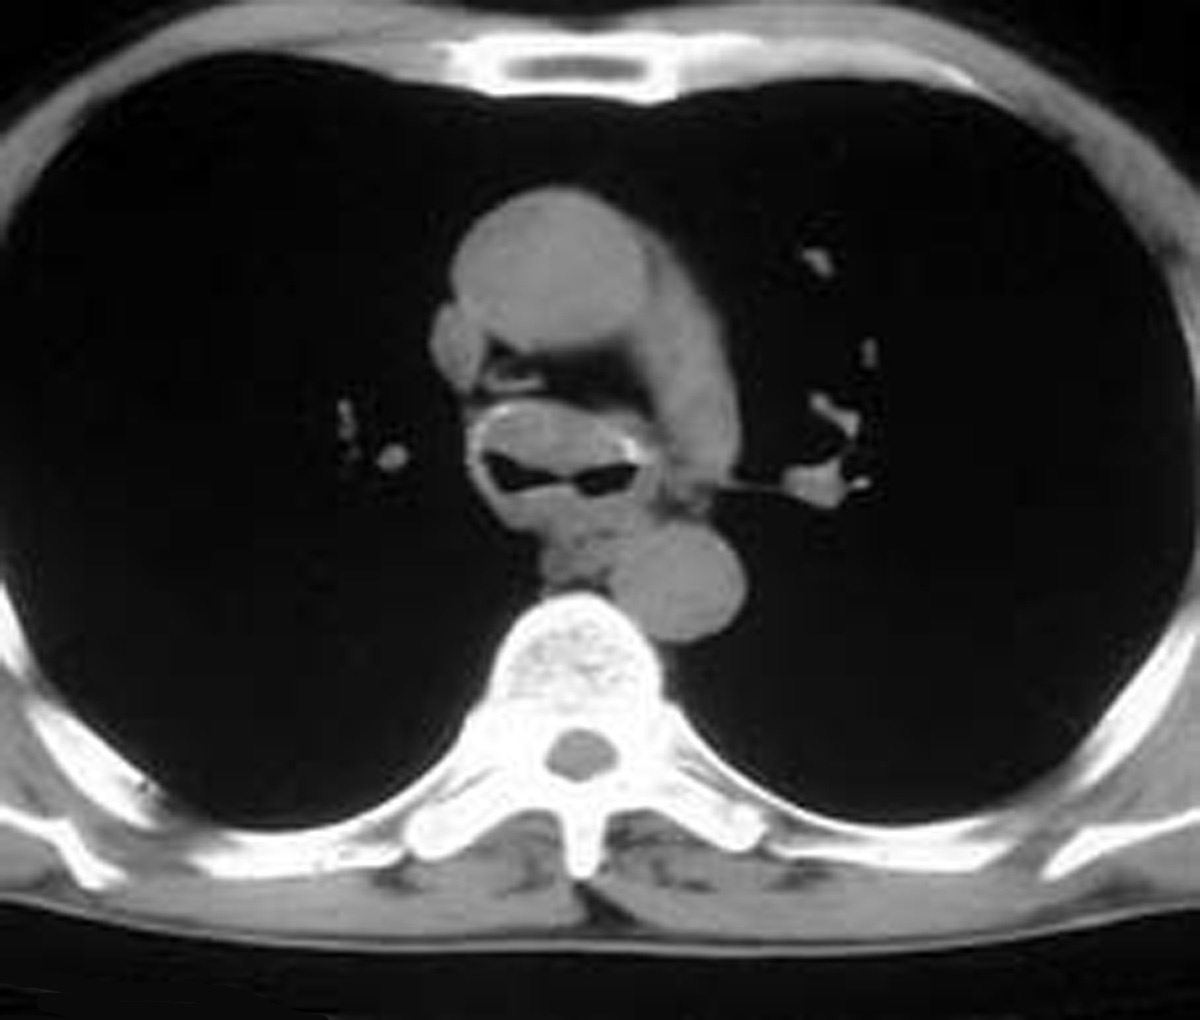

A number of indications for endoscopic treatment have been reported (Table 1) but the most frequent is lung cancer involving the airway proximal to the lobar orifices. In most patients with unresectable tumors only palliation is required [2,3] and sometimes urgent stenting during chemo-radiotherapy may be demanded; however, in selected patients a viable airway may be important as a bridge to surgery [4,5]. Patients with primary airway tumors (Figure 1) may receive benefit from endoluminal stenting if surgery is not indicated. Other tumors that occur adjacent to the airway may produce obstruction by direct invasion or extrinsic compression, including esophageal cancer possibly accompanied by tracheo-esophageal fistula (Figure 2), thyroid cancer, and other head and neck tumors, and may be successfully palliated with endoluminal treatments combined with stent placement [6].